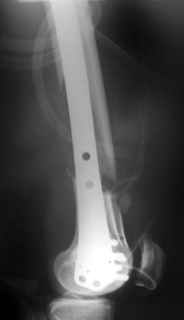

This is what we have done... As generally true for LISS look at the bone not the hardware.

There are two more srews above. The one not completely in got damaged head.